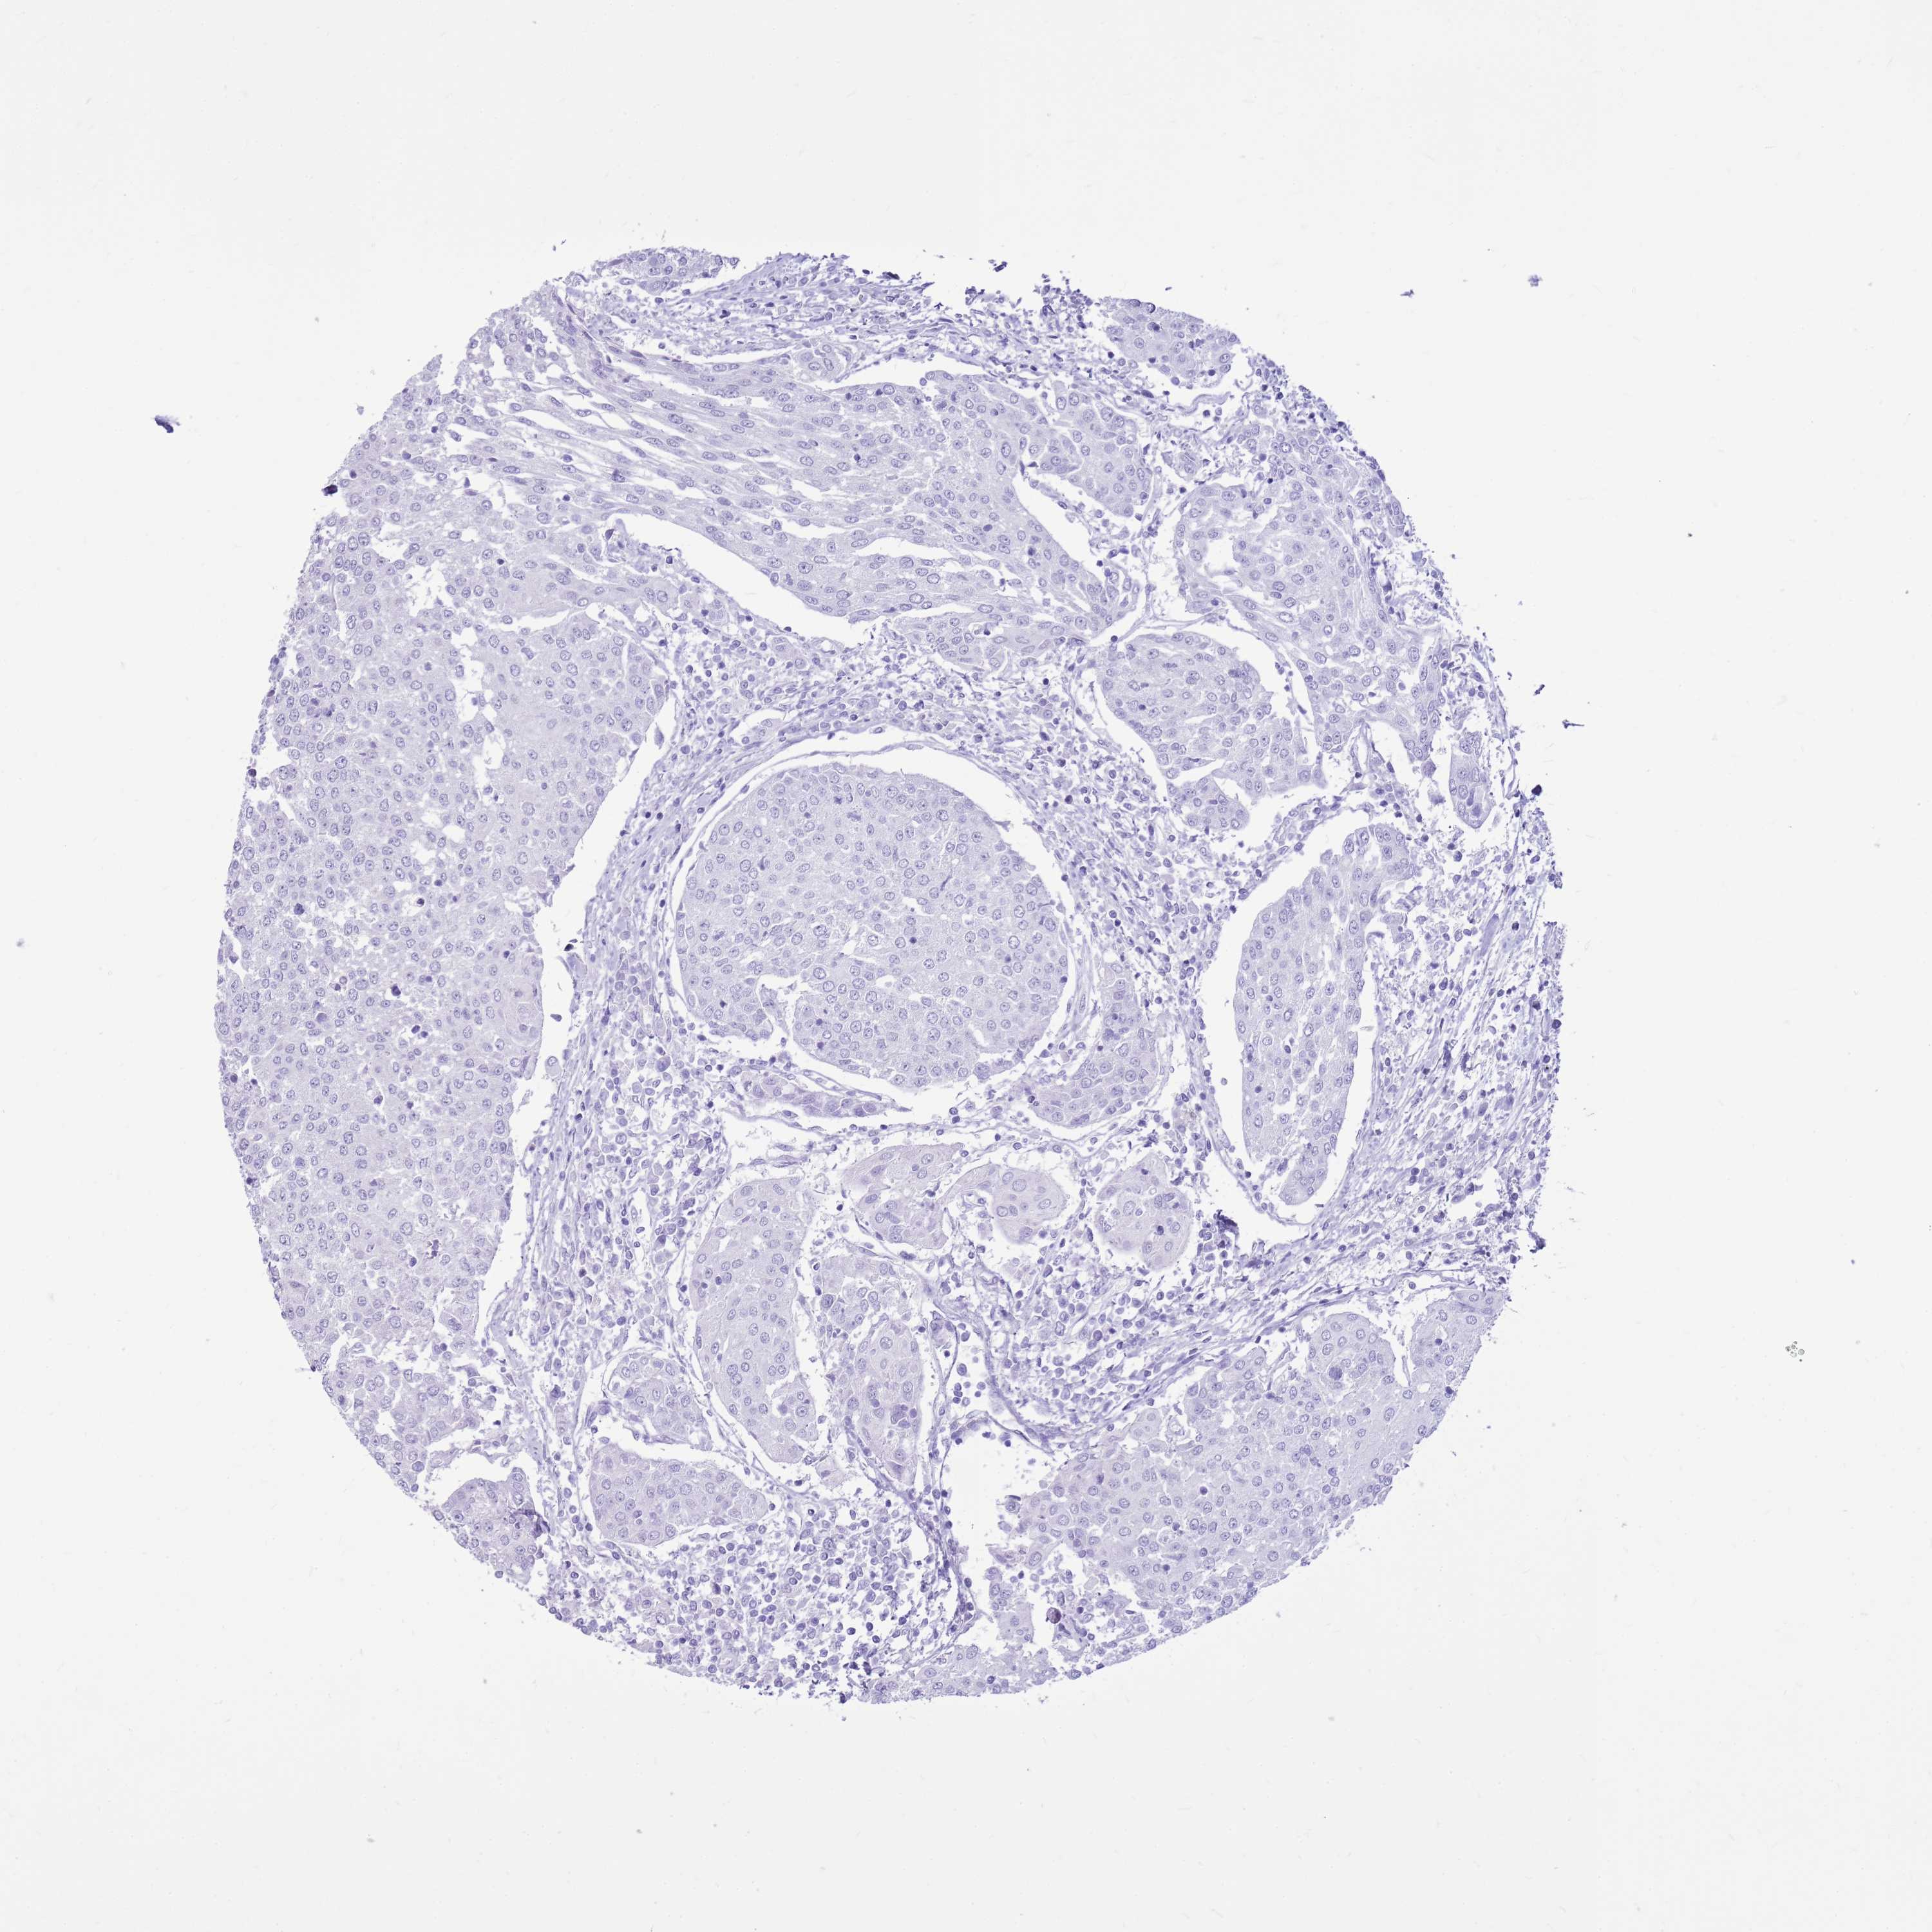

UROTHELIAL CANCER - Protein expressioni

A mouse-over function shows sample information and annotation data. Click on an image to view it in a full screen mode. Samples can be filtered based on level of antibody staining by selecting one or several of the following categories: high, medium, low and not detected. The assay and annotation is described here.

Note that samples used for immunohistochemistry by the Human Protein Atlas do not correspond to samples in the TCGA dataset.

Antibody stainingi

Antibody staining in the annotated cell types in the current human tissue is reported as not detected, low, medium, or high, based on conventional immunohistochemistry profiling in selected tissues. This score is based on the combination of the staining intensity and fraction of stained cells.

Each image is clickable and will lead to virtual microscopy that enables deeper exploration of all samples and also displays staining intensity scores, fraction scores and subcellular localization as well as patient and tissue information for each sample.

Antibody HPA024748

Antibody CAB025545

Antibody CAB047309

Urothelial carcinoma, Low grade

Urothelial carcinoma, High grade

Urothelial carcinoma, NOS